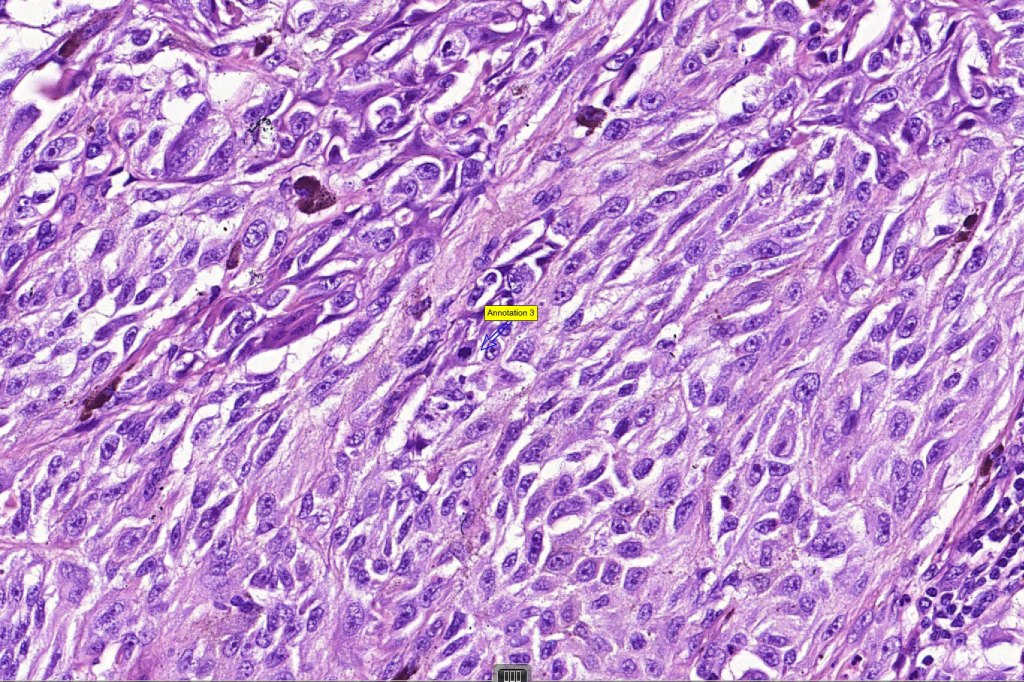

Histological features

•>5-10 mm

•Involve deep dermis or subcutis

•Asymmetrical, poorly circumscribed

•May show effacement/consumption of epidermis or ulceration

•Peripheral Pagetoid spread

•Large nodules which often show impaired maturation

•Loss of gradient with HMB45 and Ki67

•>20% Ki67 expression

•TERT promoter & PTEN mutations

•DNA copy-number variations